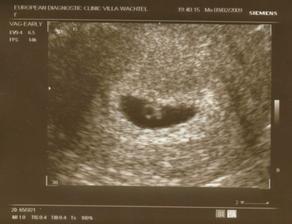

3.2.2009 kontrola u doktora - už máme i žloutkový váček,ale mimís tam ještě není vidět, pan doktor nám nakreslil, co vidíme dneska a co bude vidět příště (viz album) 🙂

9.2.2009 kontrola u doktora - je tam mimís i se srdíčkem 🙂

18.2.2009 další kontrola, mimís měří 11,9 mm, srdíčko šlape jak hodinky, máme zase fotku a opět kresbu od pana doktora jako bonus 🙂)